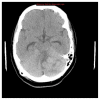

Introduction/background: Vomiting is a common chief complaint in pediatric patients seen in the Emergency Department. 1-3 Presentations include acute, chronic, and cyclic vomiting, with underlying etiologies such as toxin injection, emotional disturbances, and movement disequilibrium. 1 By understanding these various pathways, it is helpful for physicians to distinguish between gastrointestinal and non-gastrointestinal causes of vomiting. 1 Most cases of vomiting in the pediatric population are self-limiting and require only supportive treatment; however, physicians must be able to recognize red flags associated with vomiting that warrant further evaluation. 1,3 This task may be challenging for medical students and residents in emergency medicine and those with infrequent exposure to pediatric patients. Therefore, this team-based learning activity was developed to help junior learners in differentiating non-emergent and emergent cases of pediatric vomiting. This activity aids learners in formulating a differential based on age, history, and characteristics of vomiting. We also review specific causes of pediatric vomiting that physicians cannot miss including intussusception, pyloric stenosis, malrotation, intestinal atresia, and intracranial pathology.

Educational objectives: By the end of this TBL session, learners should be able to:Identify red flag symptoms that should prompt referral for urgent intervention by GI or surgical specialists.Recognize how chronicity of the vomiting can alter the differential diagnosisDescribe the varying pathways that can cause nausea and vomiting.Determine the necessity of imaging tests to confirm and possibly treat various causes of vomiting.Interpret imaging studies associated with specific causes of vomiting.